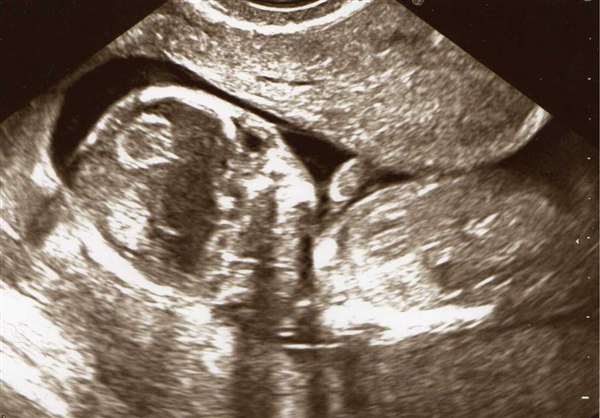

Så er dagen kommet hvor vi skal til kønsscanning og se om lille-niv er en lille pige eller lille dreng

Nu har der været nogle gæt omkring kønnet, og så tænkte jeg at jeg da kunne lave en lille gætte leg ud af det - så derfor har jeg sat billeder ind af lille-niv fra NF scanning og af min mave idag.

Vedhæftede fotos (klik for at se i fuld størrelse)